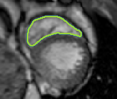

4.2 Visual assessment

We select the case that achieves the highest and lowest dice score for visual assessment. Fig. 4 shows example segmentation results where the proposed method achieved the highest agreement with the ground truth delineations. Fig. 5 shows example segmentation results where the proposed method achieved the lowest agreement with the ground truth delineations.